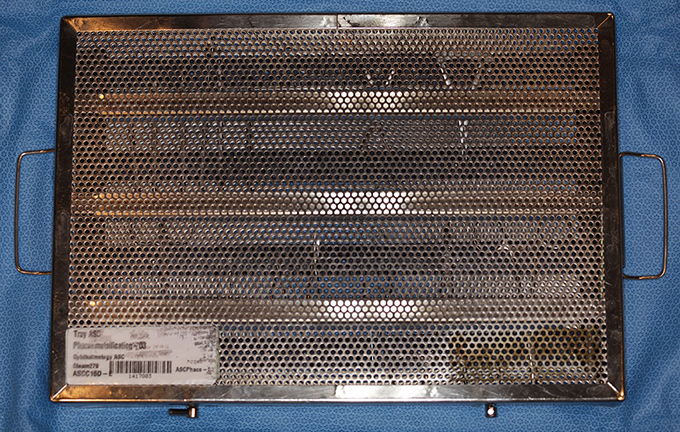

Instrument Tray with Lid, Storz E-7415